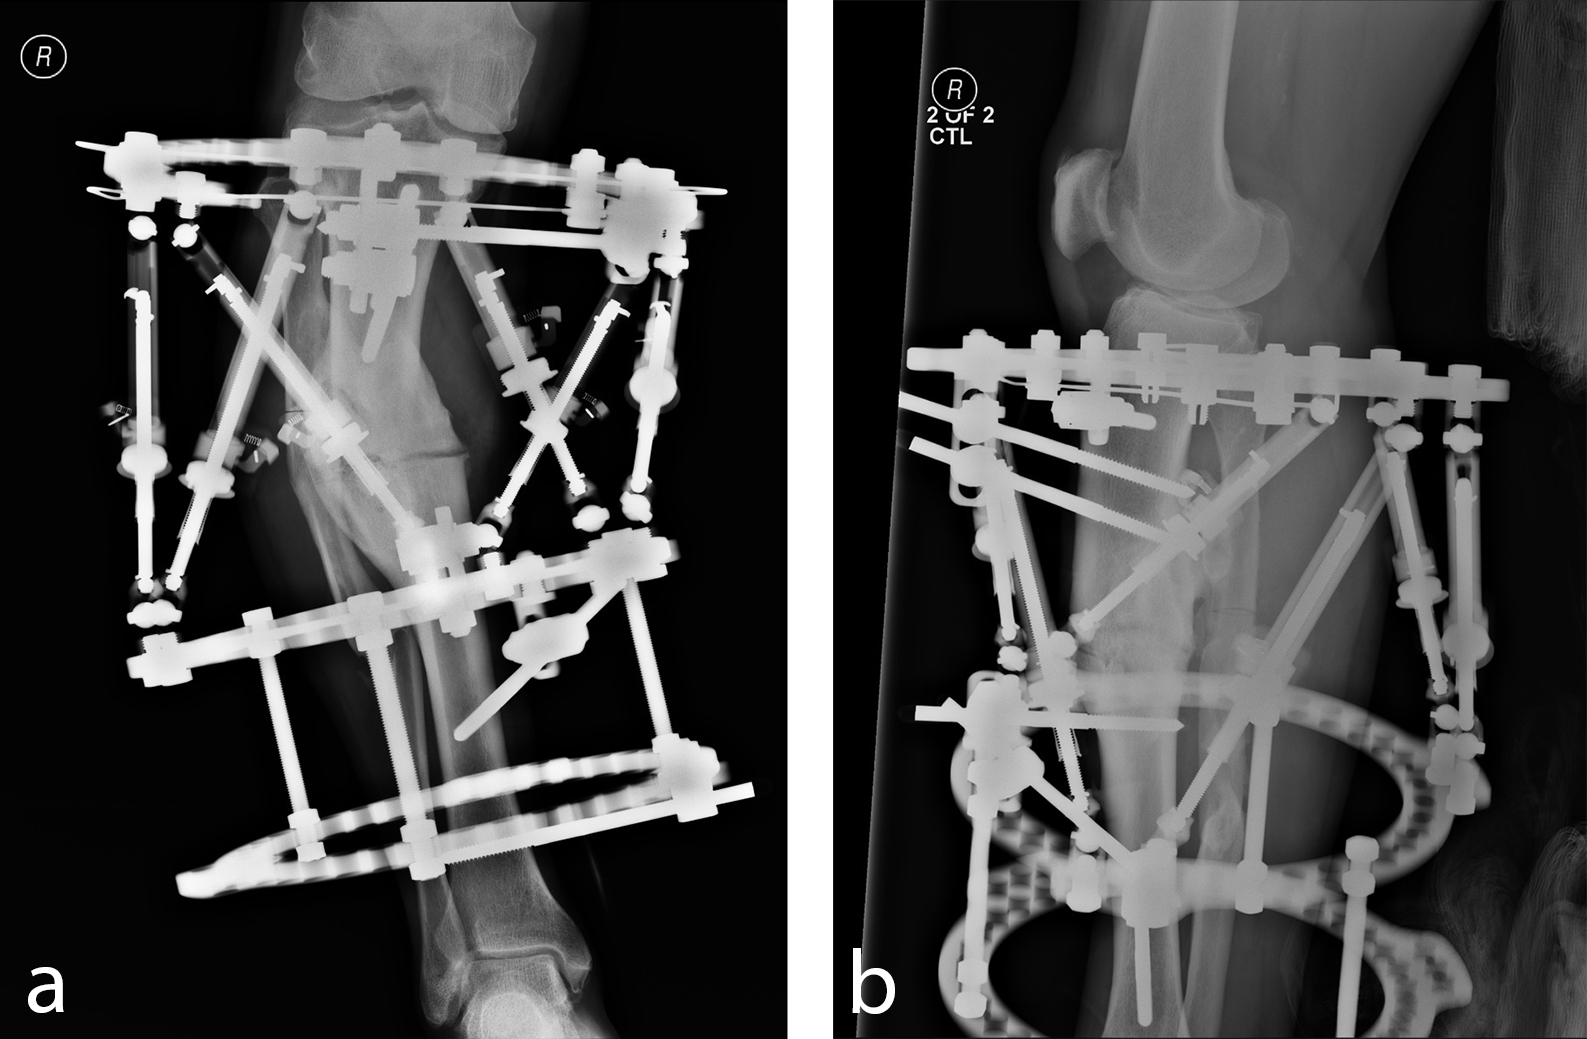

A 54-year-old man suffered bilateral tibial fractures 20 years earlier, both treated in a cast. He now experiences pain in the medial right knee. Images taken showed that both legs had substantial malunion, but the right knee caused pain because it was out of mechanical axis (Fig 11). The patient was successfully treated with the MAXFRAME system (Figs 12 to 15).